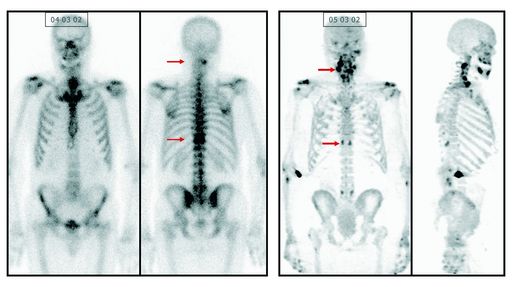

Das Nukleararzneimittel IASOflu(R) wird für funktionell

bildgebende Verfahren, zur Untersuchung von ungewöhnlichen Änderungen

der osteogenen Aktivität, indiziert. Das revolutionäre Fluorid

liefert exaktere Ergebnisse und unterstützt durch seine feinere

Detaildarstellung die Arbeit der Ärzte. Die IASON GmbH, Hersteller

Durch die Verabreichung von IASOflu(R) können Knochenmetastasen

bei Erwachsenen leichter lokalisiert und lebensrettende Maßnahmen

rascher eingeleitet werden. Weiters dient es zur Diagnose von